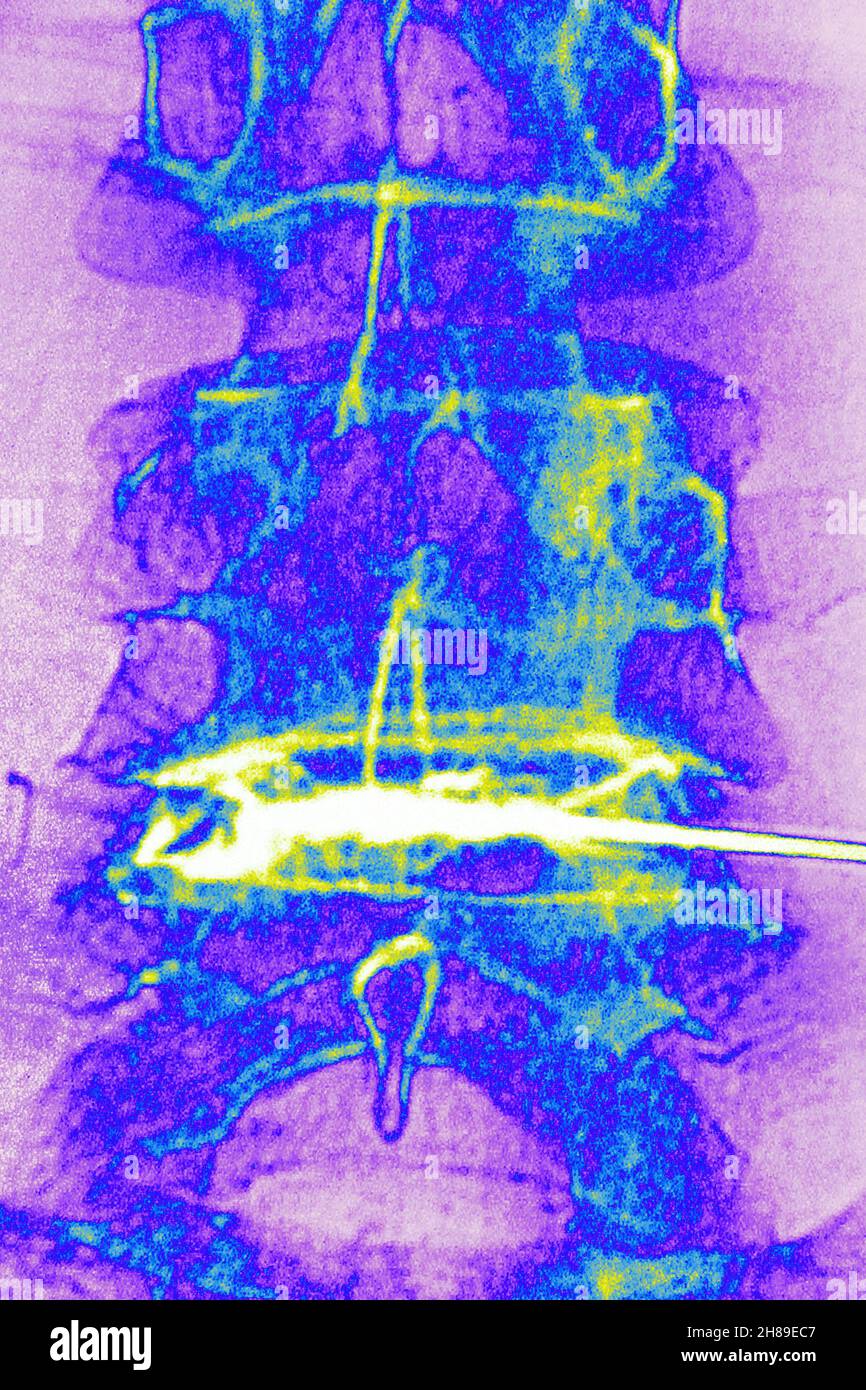

Infiltration de corticostéroïdes Banque D'Imageshttps://www.alamyimages.fr/image-license-details/?v=1https://www.alamyimages.fr/infiltration-de-corticosteroides-image452595703.html

Infiltration de corticostéroïdes Banque D'Imageshttps://www.alamyimages.fr/image-license-details/?v=1https://www.alamyimages.fr/infiltration-de-corticosteroides-image452595703.htmlRM2H89EC7–Infiltration de corticostéroïdes